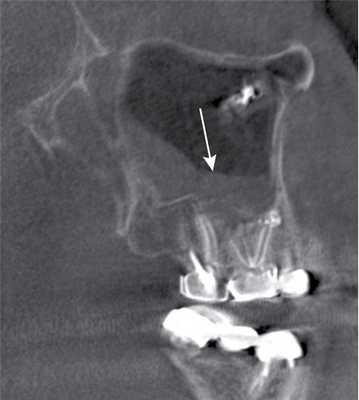

(Слева) На аксиальной КЛКТ справа и слева визуализируются добавочные устья ниже уровня соответствующих крючковидных отростков. Основные устья находятся на другом уровне и не видны на этом срезе.

(Справа) На корональной КЛКТ у этого же пациента визуализируются дополнительные устья справа и слева. Основные устья на этом срезе не видны. Обратите внимание на субтотальное снижение пневматизаци левой верхнечелюстной пазухи.

(Слева) На корональной КЛКТ (реконструкция) визуализируется добавочное переднее устье.

(Справа) На корональной КЛКТ визуализируются добавочные устья В, расположенные за основными. Картина сопоставима с таковой после хирургического вмешательства по поводу хронического синусита. Определяется утолщение слизистой оболочки В обеих верхнечелюстных пазух, обусловленное хроническим воспалением.